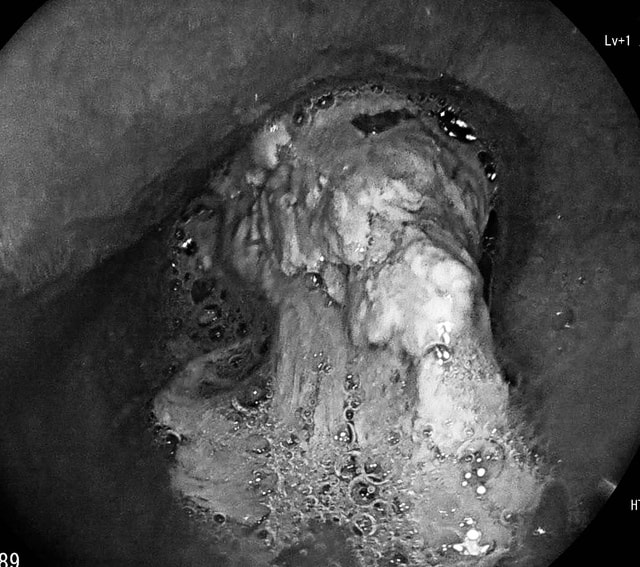

Trước đó, ông Đ.N.C. (SN 1964, trú tại xã Ninh Châu) đến viện trong tình trạng nuốt nghẹn sau bữa ăn. Bệnh nhân cho biết bản thân có tiền sử hẹp thực quản. Kết quả nội soi thực quản – dạ dày ghi nhận khối thịt lớn bít gần kín thực quản ông C.